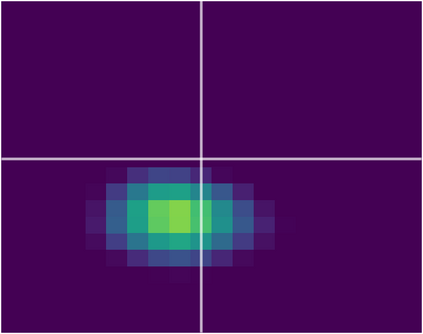

Various imaging modalities allow for time-dependent image reconstructions from measurements where its acquisition also has a time-dependent nature. Magnetic particle imaging (MPI) falls into this class of imaging modalities and it thus also provides a dynamic inverse problem. Without proper consideration of the dynamic behavior, motion artifacts in the reconstruction become an issue. More sophisticated methods need to be developed and applied to the reconstruction of the time-dependent sequences of images. In this context, we investigate the incorporation of motion priors in terms of certain flow-parameter-dependent PDEs in the reconstruction process of time-dependent 3D images in magnetic particle imaging. The present work comprises the method development for a general 3D+time setting for time-dependent linear forward operators, analytical investigation of necessary properties in the MPI forward operator, modeling aspects in dynamic MPI, and extensive numerical experiments on 3D+time imaging including simulated data as well as measurements from a rotation phantom and in-vivo data from a mouse.